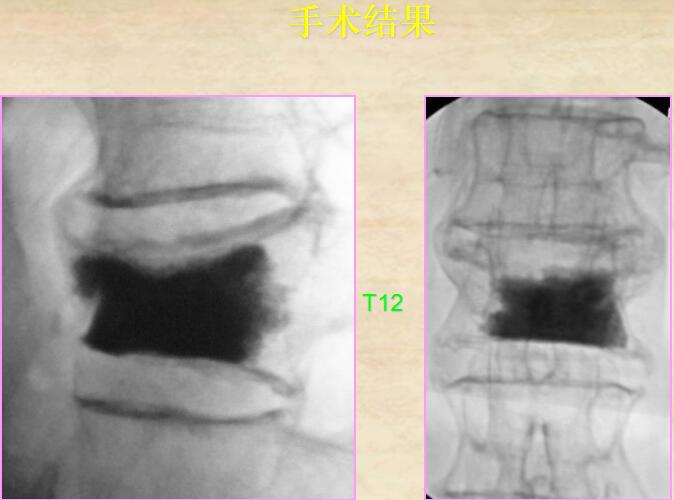

5、手術結果